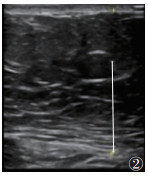

1.2 仪器与方法615例均行超声检查,采用GE20彩色多普勒超声诊断仪。受试者取仰卧位,伸展右上肢至头部,充分扩展肋间隙。选用凸阵探头(频率2~5 MHz),垂直放置探头,通过肋间隙对肝Ⅴ段行常规超声检查,并根据肝脏回声强度、肝肾回声对比、肝内血管和膈肌的清晰度,判断脂肪肝程度(无、轻度、中度和重度)[4];测量内脏脂肪厚度(visceral fat thickness,VFT),将探头置于脐上1 cm,测量双侧腹直肌间腹白线至腹主动脉前壁的距离[5](图 1),结果取双侧平均值。使用线阵探头(频率2~9 MHz)测量皮下脂肪厚度(subcutaneous fat thickness,SFT):将探头置于脐上1 cm,左右移动探头测量腹部两侧皮肤至腹直肌外缘距离(图 2),最终结果取双侧平均值[5]。激活UGAP模式,嘱患者屏住呼吸3~5 s,记录不同帧上连续回波UGAP-AC平均值,注意避开胆管、血管等伪影(图 3)。

| 图 2 常规超声测量皮下脂肪厚度(SFT)示意图 |